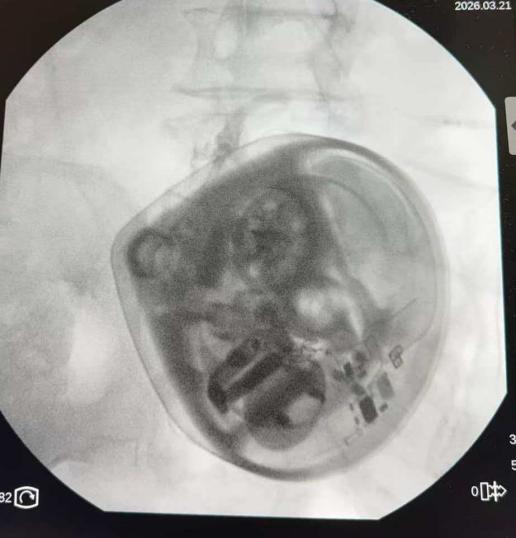

TDD技术,也被称为“全植入式镇痛泵”,是目前国际公认的治疗顽固性疼痛的“终极武器”。

其运行机制可类比军事行动中的“精准打击”,通过微创手术,将一个可储药的泵体植入患者腹部皮下,并将一根纤细的导管精准置入蛛网膜下腔(鞘内)。药物不再经过胃肠道吸收或血液循环,而是直接作用于脊髓和大脑的疼痛信号“指挥中枢”。

在邹定全主任精准操作及邵阳市中医医院疼痛团队的密切配合下,手术过程顺利。术后,患者的疼痛评分从术前的重度疼痛(8-9分)迅速降至轻度或无痛状态(0-2分)。